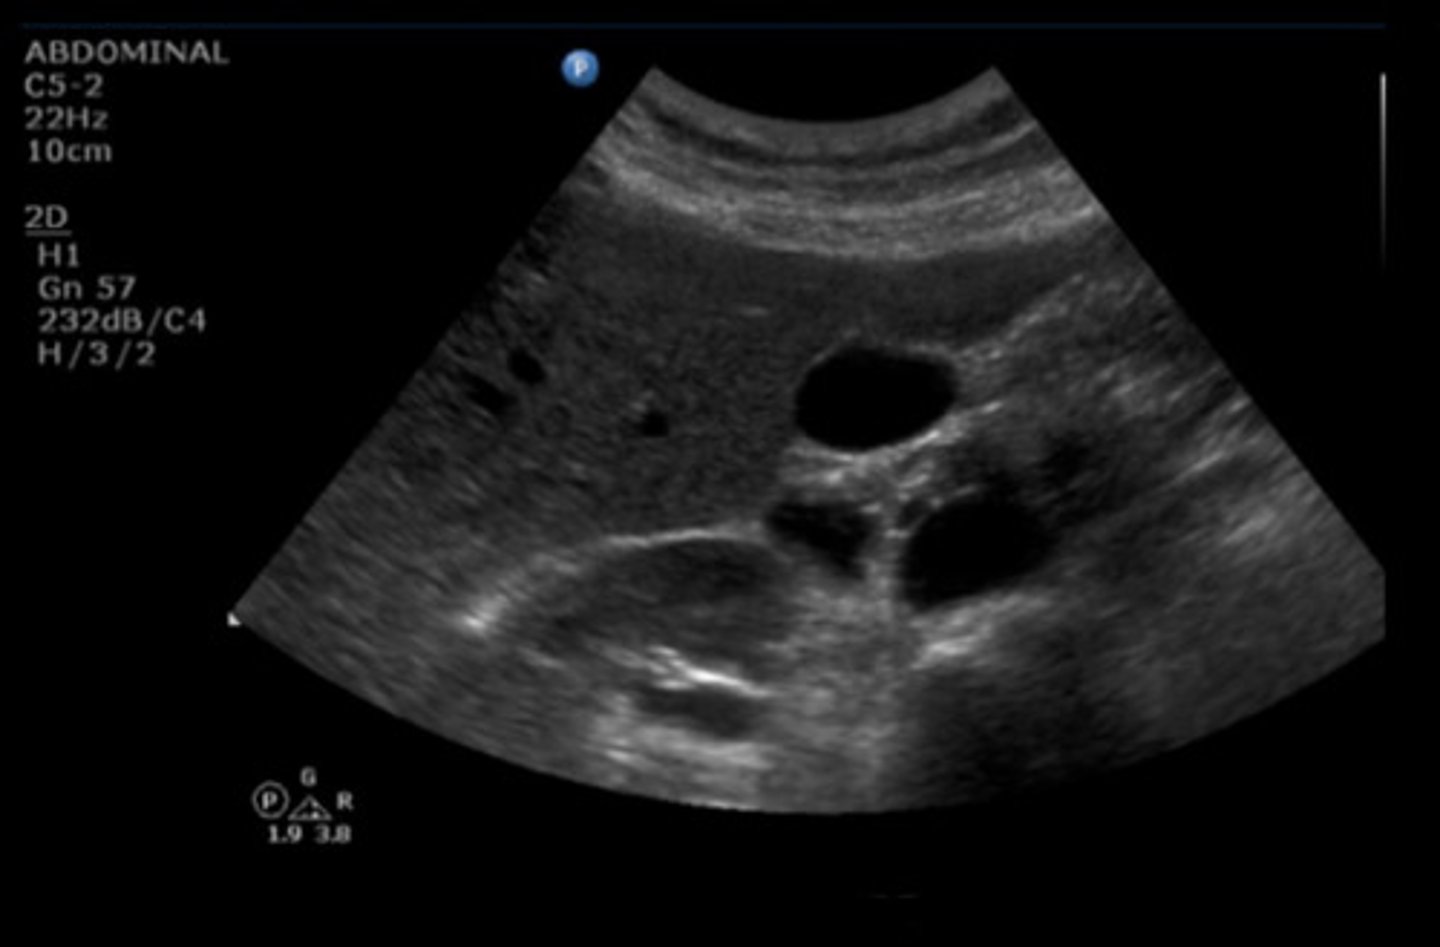

TRV GB FUNDUS SUPINE

Identify the following;

<p>Identify the following;</p>